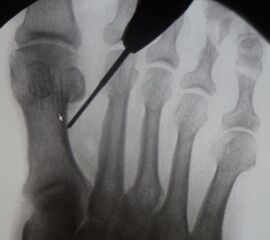

• Die Operationsplanung erfolgt anhand der Röntgenaufnahmen des Vorfußes unter Belastung in 2 Ebenen. Für die Verfahrenswahl sind wichtig der Intermetatarsalwinkel und die Breite des Os metatarsale, der Hallux valgus Winkel, der distalen Gelenkflächenwinkels (Distal Metatarsal Articular Angulation - DMAA), des Metatarsaleindex und Sesambeinposition (Abb. 1).

• Bildverstärker für intraoperative Kontrollaufnahmen 3.

• Bildverstärker.

• Gegebenenfalls röntgendichte Handschuhe.

• Positionierung des Bildverstärkers im 90° Winkel zur Fußlängsachse (Abbildung 4).

Die Fräse wird auf eine Drehzahl von 3000 – 5000 RPM eingestellt.